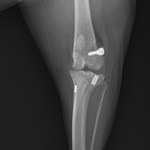

ラテラルスーチャー設置:

・外側大腿顆後方(Fabella近位)に4.0横穴付きスクリューを埋入。

・脛骨内側にエンドボタンを装着、ナイロン糸を8の字状に通過

・膝関節を軽度屈曲位で適切なテンションをかけてチタンクランプで締結。